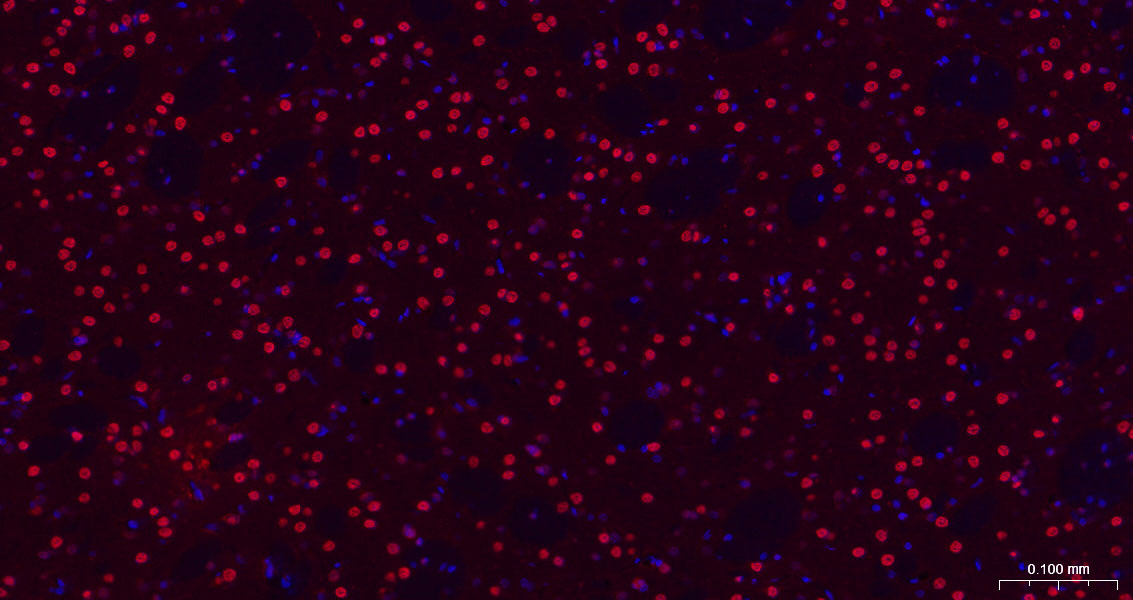

Paraformaldehyde-fixed, paraffin embedded Mouse Cerebrum; Antigen retrieval by boiling in sodium citrate buffer (pH6.0) for 15 min; The section was incubated with HES1 Monoclonal Antibody, Unconjugated (bsm-52568R) at 1:200 overnight at 4°C. Followed by conjugated Goat Anti-Rabbit IgG antibody (Red, bs-0295G-BF594), DAPI (blue, C02-04002) was used to stain the cell nuclei.